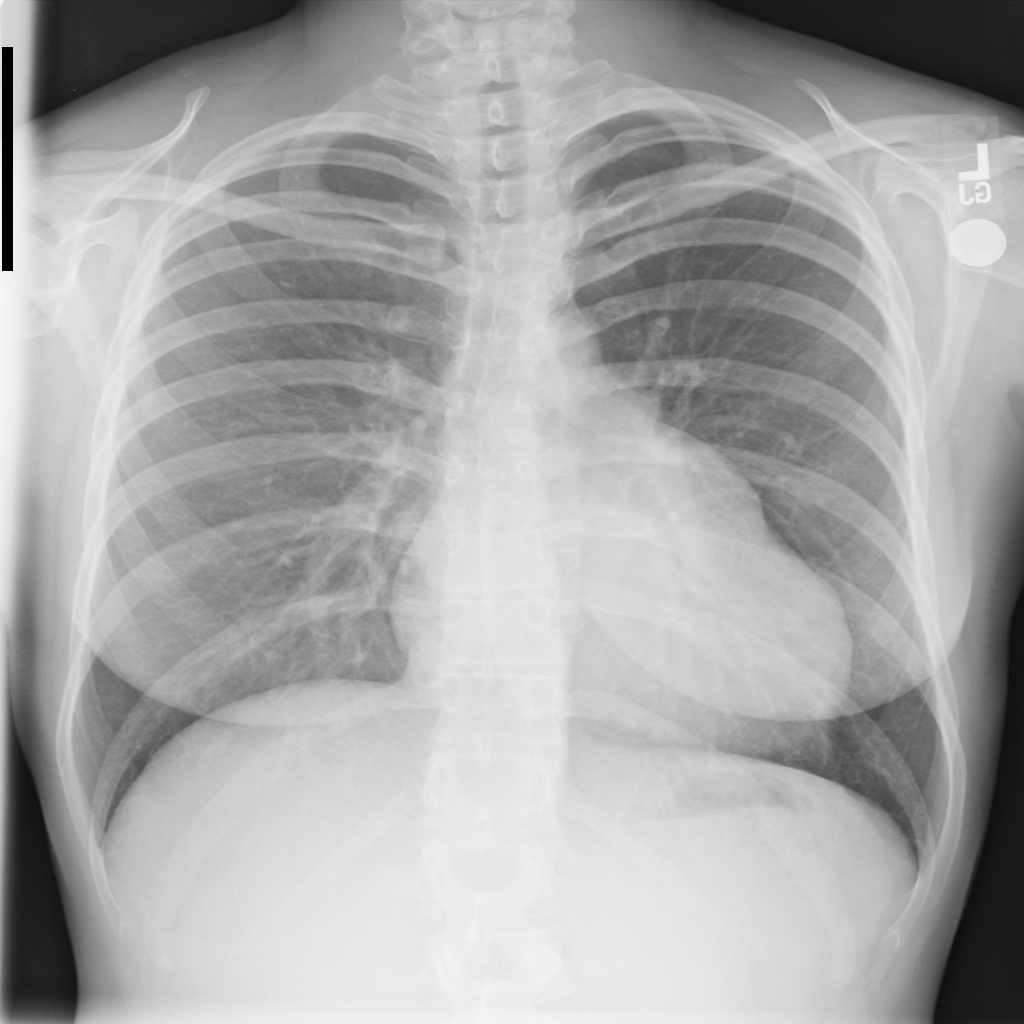

PAT-AE5C · IMG-000Cardiomegaly

PAT-AE5C · IMG-000

PA